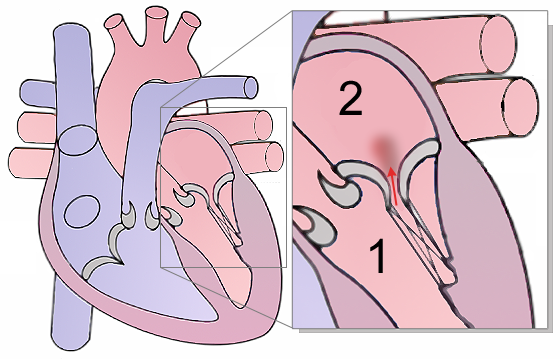

Chronic rheumatic heart disease develops when rheumatic fever-related valve scarring leads to stenosis with the classic fish-mouth appearance.

In chronic rheumatic heart disease, the chordae tendineae and cusps thicken as a result of the mitral valve being involved almost always.

Mitral valve prolapse is the ballooning of the mitral valve into the left atrium during systole.

The narrowing of the mitral valve orifice is known as mitral stenosis.